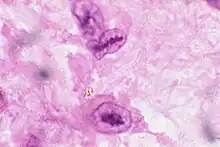

Anitschkow cell

In pathology, Anitschkow (or Anichkov[1]) cells are often cells associated with rheumatic heart disease.[2] Anitschkow cells are enlarged macrophages found within granulomas (called Aschoff bodies) associated with the disease.[2]

The cells are also called caterpillar cells, as they have an ovoid nucleus and chromatin that is condensed toward the center of the nucleus in a wavy rod-like pattern that to some resembles a caterpillar.[2] Larger Anitschkow cells may coalesce to form multinucleated Aschoff giant cells.[2] Anitschkow cells were named after the Russian pathologist Nikolay Anichkov.